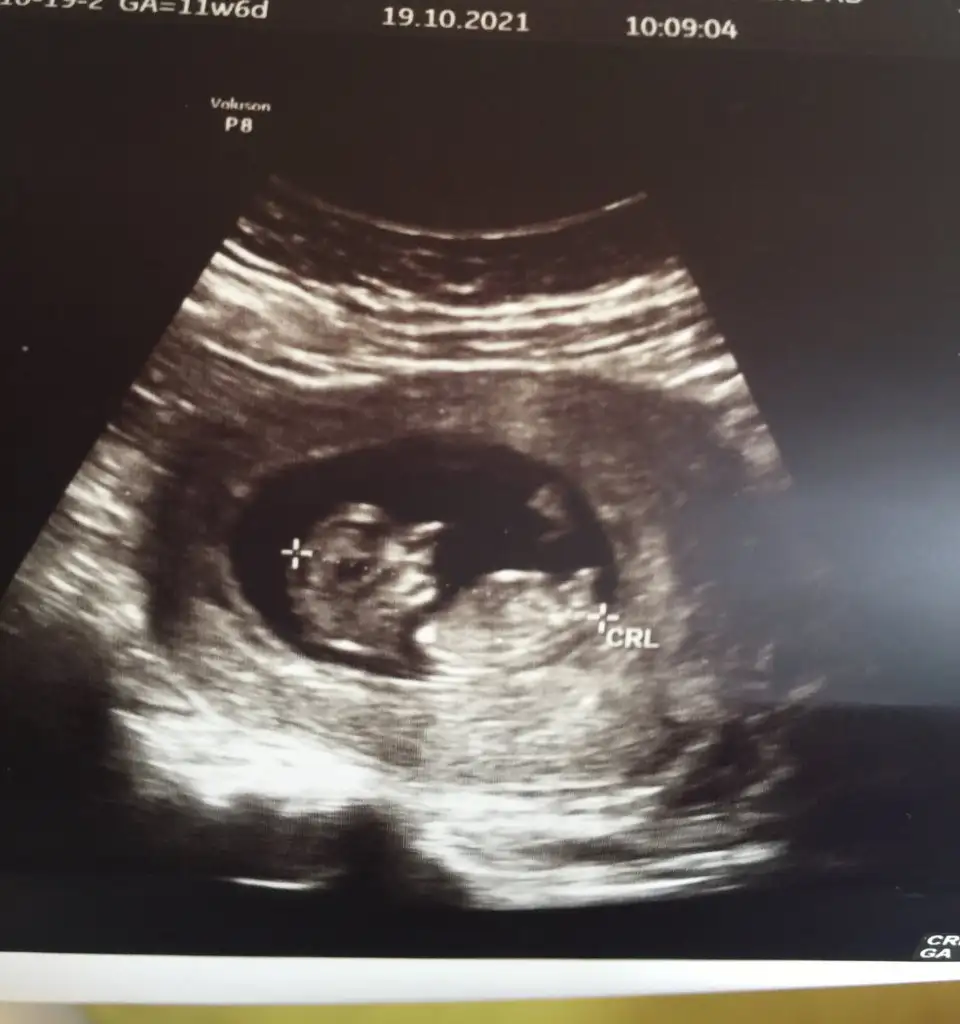

Ikra meyra Ikra meyra Merhaba, bu ultrason goruntuleri son adet tarihine gore 11+5, ultrason olcumune gore 12+3. Acaba cinsiyet icin bi yorum da bulunabilir misiniz ? 😇 Simdiden tesekkur ederim.